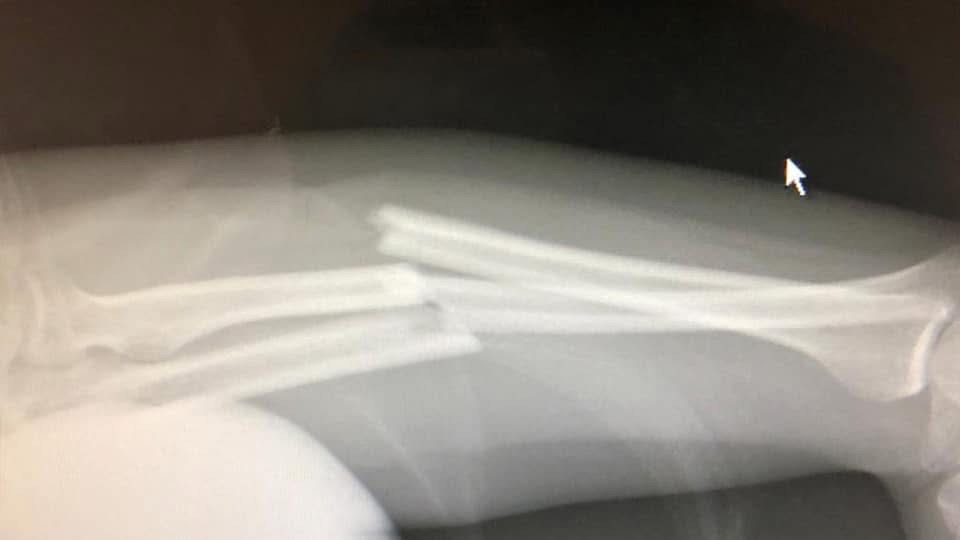

Because life is life, I fell over in the shower and broke my arm, so I couldn’t go to the opening.

When I came out of surgery with bones bolted together and my arm in a cast, I went down to AKG to see my show and pick up some unused work. I arrived to find that the only existing build of ‘Are You Still Watching?’ was no more. Something had happened to the computer, and it wouldn’t turn on. The screen was black and a single red light blinked at me from the tower. Since it wasn’t even my computer, I wasn’t sure what to do, so I hauled it home to Leamington and left it with the relative who owned it to take it over to a repair shop and get it assessed. That was February 2020. Guess what happened next?